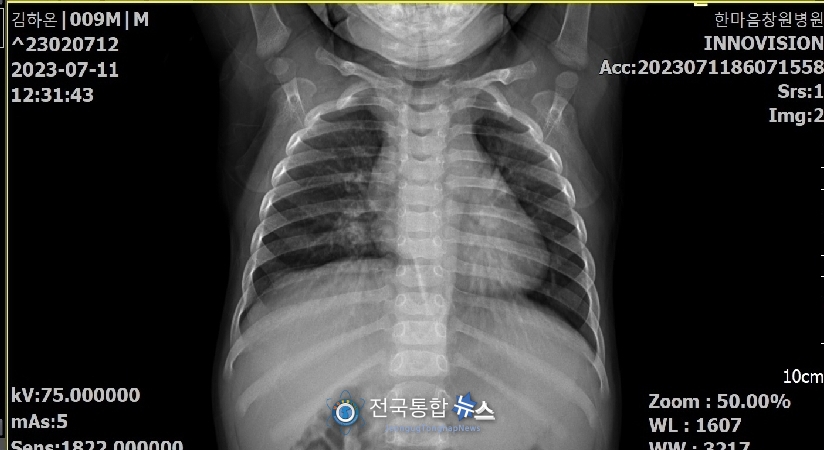

그런데, 아래의 한마음창원병원에서 찍은 사진에는 늑골 골절 흔적을 발견하게 되었으며, 다시 한번 착잡하고 억압이 터지는 마음을 감출 수가 없었다.

이러한 진실이 있음에도 불구하고 경찰관은 부모에 대해 덤태기 씌우려는 행위를 멈추지 않았고, 결국 이 두 부모는 변호사를 선임하여 정식으로 고소장(늑골 골절)을 제출하고 엄중하고 신속하게 조사해줄 것을 요청했으나, 경찰관은 국과수에 의뢰한 후, 결과가 나오면 조사를 하겠다며 증거가 인멸될 때까지 기다리고 있는 상황이다.